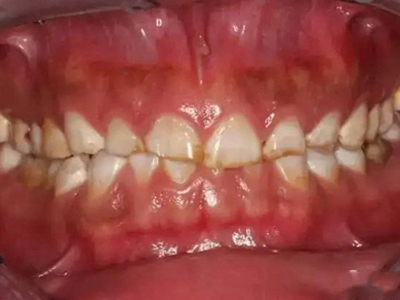

牙齿

黄斑 · 出血

酸蚀症牙齿有黄斑牙龈出血图

发生酸蚀症时,牙齿会有黄斑形成,境界不十分清楚,主要分布在牙根及牙缝处,靠近患牙的牙龈有轻微出血。该病的发生与口腔长期接触酸性物质有关。